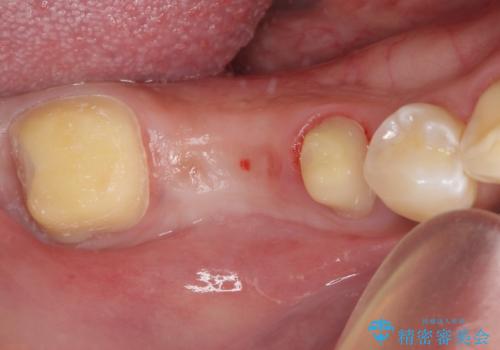

- 以前他院にて、保険診療で治療した金属のブリッジをやり替え希望の患者様です。

奥歯であっても、大きく笑うと金属色が目立ちます。

金属ブリッジを除去し、虫歯を完全に除去し、形を整え、

精度の高いシリコーン材料にて型どりをしました。